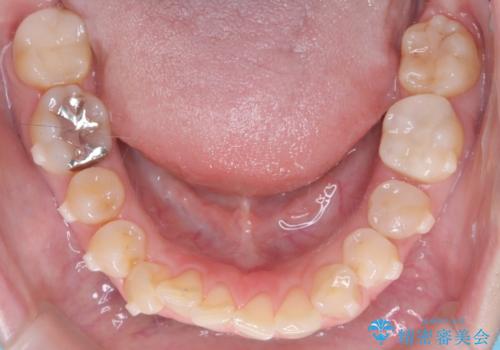

- 下の前歯のデコボコ(叢生)を気にされてご来院されました。精密な検査の結果、下の前歯を並べるスペースが不足していることが判明。患者様のご希望から、透明で目立ちにくい**インビザライン(マウスピース矯正)による治療計画を立案しました。主に歯の側面をわずかに削るIPR(歯間乳頭保護下ストリッピング)**などでスペースを確保し、下の前歯の叢生を解消することを目指します。

今回の矯正治療では、透明なマウスピース型の装置インビザラインを使用しました。目立たず、取り外しが可能なため、日常生活にほとんど影響なく治療を進めることができました。治療は、緻密に計算された計画に基づき、IPRなどで必要なスペースを確保しながら、下の前歯をスムーズに移動。これにより、長年の悩みであった下の前歯のデコボコが解消され、清掃しやすい、整った歯並びを獲得していただけました。